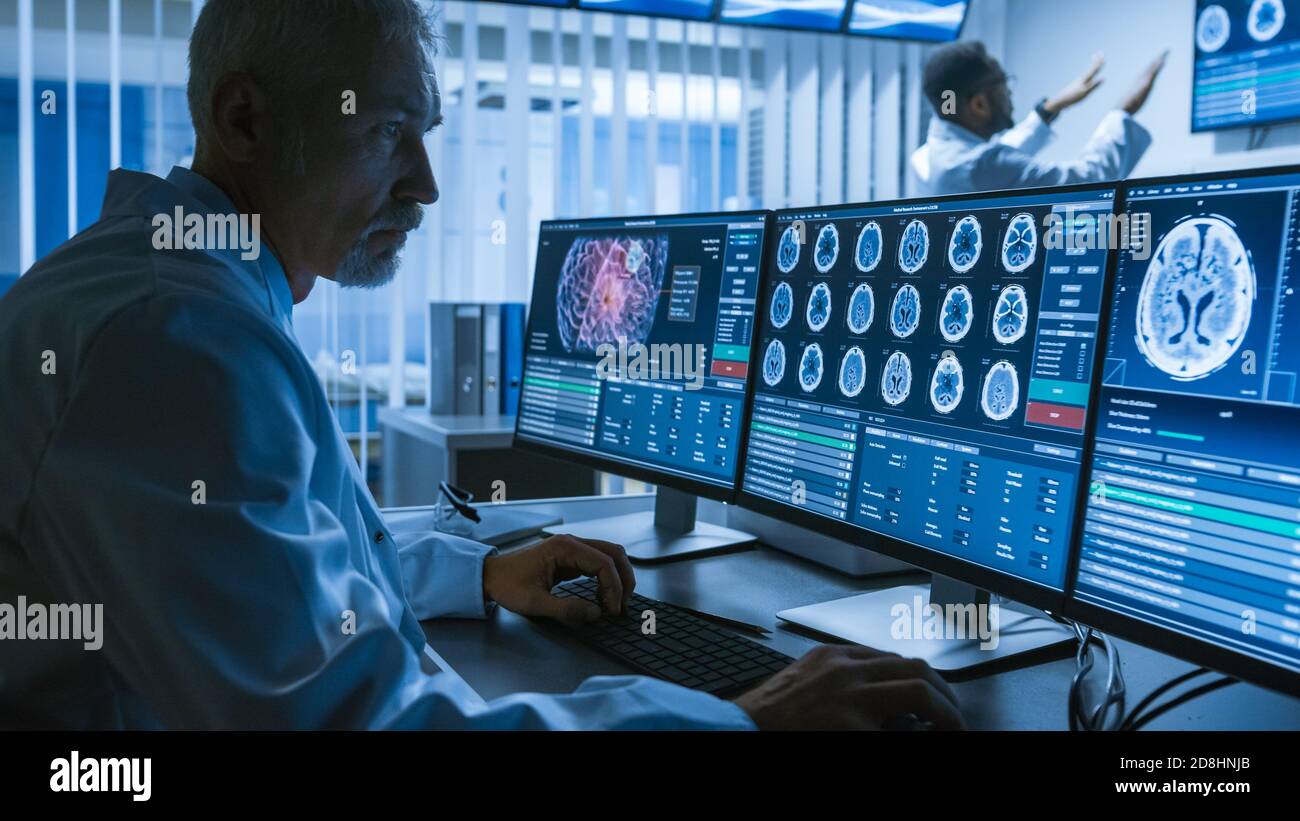

Scientifique médical travaillant avec des images CT Brain Scan sur un ordinateur personnel en laboratoire. Neurologues du Centre de recherche neurologique travaillant sur un Banque D'Imageshttps://www.alamyimages.fr/image-license-details/?v=1https://www.alamyimages.fr/scientifique-medical-travaillant-avec-des-images-ct-brain-scan-sur-un-ordinateur-personnel-en-laboratoire-neurologues-du-centre-de-recherche-neurologique-travaillant-sur-un-image383935506.html

Scientifique médical travaillant avec des images CT Brain Scan sur un ordinateur personnel en laboratoire. Neurologues du Centre de recherche neurologique travaillant sur un Banque D'Imageshttps://www.alamyimages.fr/image-license-details/?v=1https://www.alamyimages.fr/scientifique-medical-travaillant-avec-des-images-ct-brain-scan-sur-un-ordinateur-personnel-en-laboratoire-neurologues-du-centre-de-recherche-neurologique-travaillant-sur-un-image383935506.htmlRF2D8HNJA–Scientifique médical travaillant avec des images CT Brain Scan sur un ordinateur personnel en laboratoire. Neurologues du Centre de recherche neurologique travaillant sur un

Prise de vue au-dessus de l'épaule d'un scientifique médical senior travaillant avec des images CT Brain Scan sur un ordinateur personnel en laboratoire. Neurologues en recherche Banque D'Imageshttps://www.alamyimages.fr/image-license-details/?v=1https://www.alamyimages.fr/prise-de-vue-au-dessus-de-l-epaule-d-un-scientifique-medical-senior-travaillant-avec-des-images-ct-brain-scan-sur-un-ordinateur-personnel-en-laboratoire-neurologues-en-recherche-image383935507.html

Prise de vue au-dessus de l'épaule d'un scientifique médical senior travaillant avec des images CT Brain Scan sur un ordinateur personnel en laboratoire. Neurologues en recherche Banque D'Imageshttps://www.alamyimages.fr/image-license-details/?v=1https://www.alamyimages.fr/prise-de-vue-au-dessus-de-l-epaule-d-un-scientifique-medical-senior-travaillant-avec-des-images-ct-brain-scan-sur-un-ordinateur-personnel-en-laboratoire-neurologues-en-recherche-image383935507.htmlRF2D8HNJB–Prise de vue au-dessus de l'épaule d'un scientifique médical senior travaillant avec des images CT Brain Scan sur un ordinateur personnel en laboratoire. Neurologues en recherche